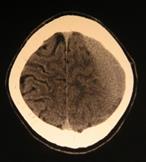

Рис.38. КТ-граммы ребенка с гидроцефалией тяжелой степени, ЛКИ=53%,

после операции нормализация внутричерепных взаимоотношений, ЛКИ= 3,2%.